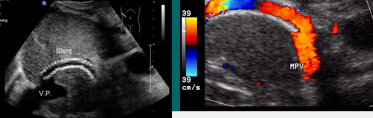

trans jugular intrahepatic portocaval shunt

TIPS